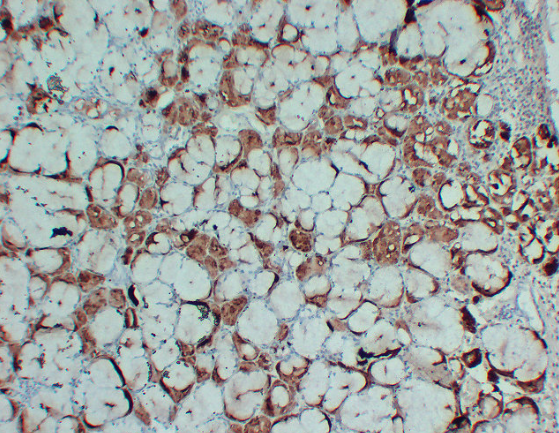

IHC (Immunohiostchemistry)

(Immunohistochemistry analysis of paraffin-embedded Human Skin using GCDFP 15 antibody.High-pressure and temperature Sodium Citrate pH 6.0 was used for antigen retrieval.)